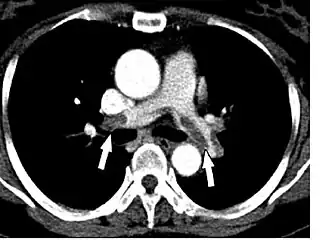

- Le scanner spiralé des artères pulmonaires[13] ou angioscanner des artères pulmonaires : un produit de contraste iodé est injecté en intraveineux. Le mouvement rotatif et longitudinal (caractère spiralé) de la tête du scanner permet de bien visualiser les artères pulmonaires proximales et moyennes et un peu moins bien leur distalité. C’est un excellent examen de diagnostic positif et de gravité, même si les risques liés à l’emploi de produits iodés et la radiation persistent. Il est moins invasif que l'angiographie conventionnelle. Il permet aussi l'évaluation de plusieurs autres structures intrathoraciques (aorte et médiastin, poumon, plèvre), en plus de l'évaluation des artères pulmonaires. Il est considéré souvent comme le nouvel examen de référence.